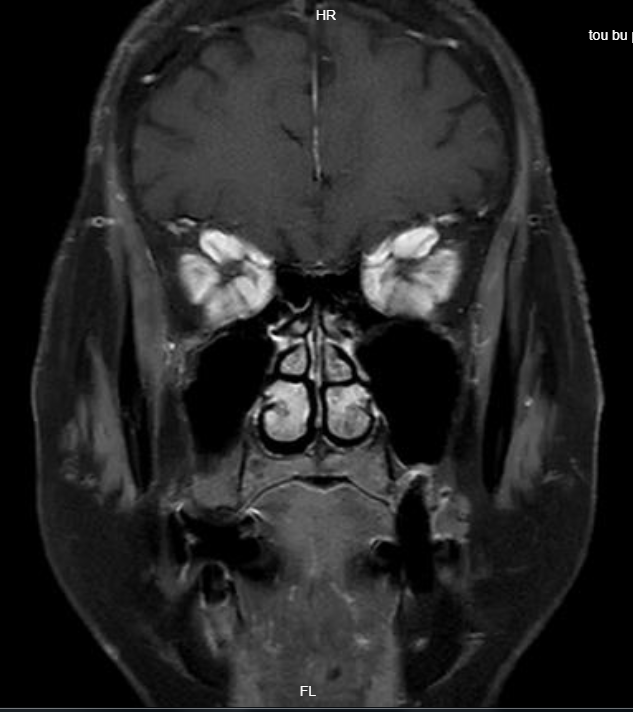

入院后,医务人员予以完善相关检查,进一步明确诊断,影像学检查提示眶尖拥挤征象明显,考虑患者视力下降原因为甲状腺相关性眼病视神经病变(DON),眼科主任冯少颖团队经过了周密的检查、评估,考虑患者有手术指征,决定联合耳鼻咽喉头颈外科团队“双管齐下”解决难题,双方团队密切配合,开展经鼻内镜下眶内侧壁减压术。该术式采用鼻内镜微创技术,和外路手术相比具有创伤更小、出血更少、安全有效、不影响美观,术后恢复更快等优势,是目前较为适合李阿姨情况的治疗方案。